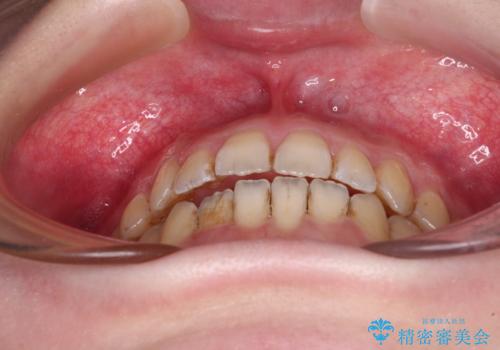

オープンバイトと前歯のデコボコをインビザライン矯正で解消

- 前歯の開咬を気にして来院された患者様です。

開咬の治療は、前歯を閉じるように動かすとともに、上下臼歯を圧下(骨内にめり込ませる)させることで進めて行きます。

インビザラインは臼歯の圧下を効果的に行えるため、インビザラインを用いて矯正治療を行うこととしました。